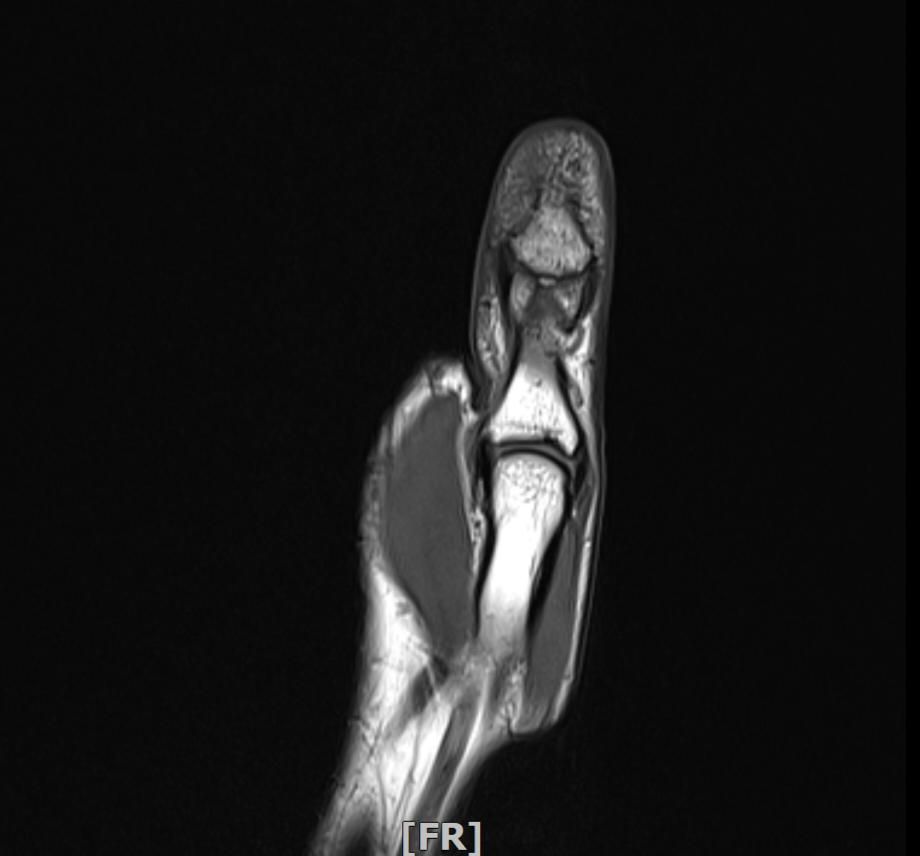

mri 엄지손가락 미세골절 여부확인

공구에 왼손이 말려서 엄지를 다쳤습니다 응급실에서 부목고정 조치후 이틀후 mri촬영 하였습니다.

엄지손가락 뼈가 자주 욱씬거리는데 미세골절 여부 확인 부탁드립니다.

• 2번 째 사진

Mri는 연부조직 확인에 강하지만 미세 골절은 일반적으로 엑스레이나 CT에서 더 잘보입니다. 다만 골수 부종이 보인다면 골절 가능성을 시사할 수 있습니다 mri판독 결과에서 골절선이나 골수 부종 유무를 확인해야 정확한 판단이 가능합니다. 정확한 진단은 반드시 영상의학과 전문의의 판독을 통해 받아야 합니다!

우선 현재로썬 MRI 사진으론 정확한 판단을 하긴 어렵지만 주변 연부조직의 손상이 보여집니다.

다만 미세골절 같은 경우는 여러 방면의 판독이 필요하므로 정확한 판독은 병원에 내원하셔서 MRI 촬영을 한 병원에 판독지를 받으시고 전문의에 판독을 받으시길 적극 추천드립니다.